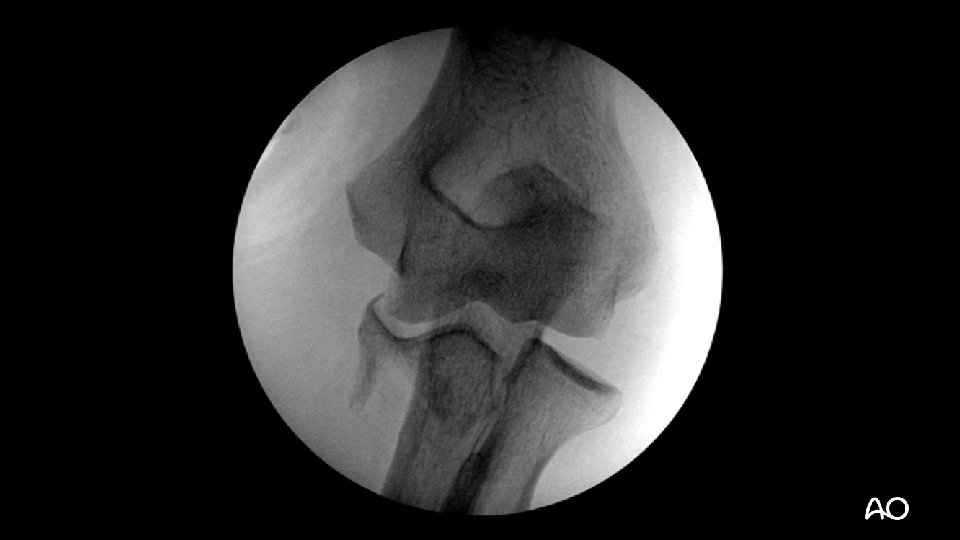

Varus posteromedial fracture dislocation • Recently described injury pattern • Failure to recognize can result in poor outcomes (arthrosis) • Easy to overlook (occasionally small coronoid fractures)

Varus posteromedial fracture dislocation Courtesy of David Ring • Stress views demonstrate that the LCL is ruptured and the elbow is unstable • Results can be poor without operative treatment

Varus posteromedial fracture dislocation—surgical tactic • Medial approach to elbow: • Split FCU, mobilize ulnar nerve • Sacrifice first motor branch? (Paulos et al [Surg Radiol Anat. 2015; 37: 1043– 1048]) • Dissect anterior to MCL • Buttress plating +/- lag screw(s) for coronoid • Stress elbow and repair LCL if instability remains: • Kocher approach